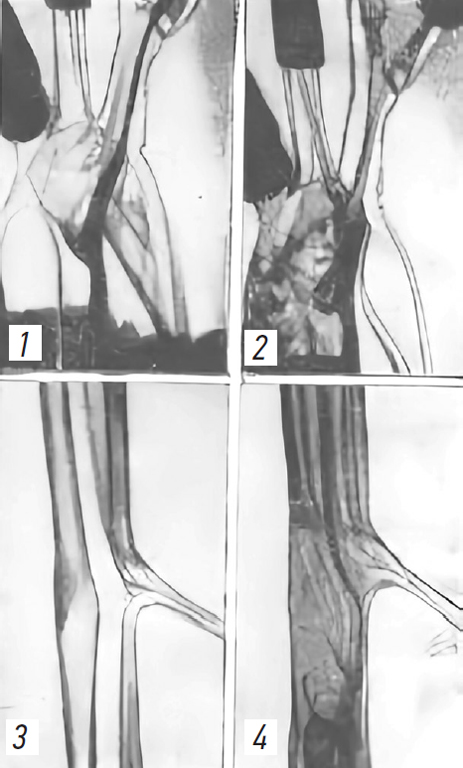

При резком выбросе крови при восстановлении нормального кровотока в артерии резко повышается градиент линейной скорости движения жидкости, что приводит к формированию локальных завихрений в толще жидкости и моментному проявлению турбулентного типа течения (рис. 7) [14, 15].

Рис. 7. Переход ламинарного типа течения в турбулентный в «дуге» аорты (1, 2) и в области брюшной аорты (3, 4) (по Савицкому И.Л. 1974) [15] (рис. 11).